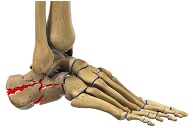

Diploma Orthopedics, Fellowship in Foot & Ankle Surgery from Vadodara, Chennai, Spain, U.K.

1st and only exclusive foot & Ankle surgeon of Saurashtra-Kutch region. Practicing orthopedics since 2014 with dedicated practice of ankle and foot surgeon since 2021